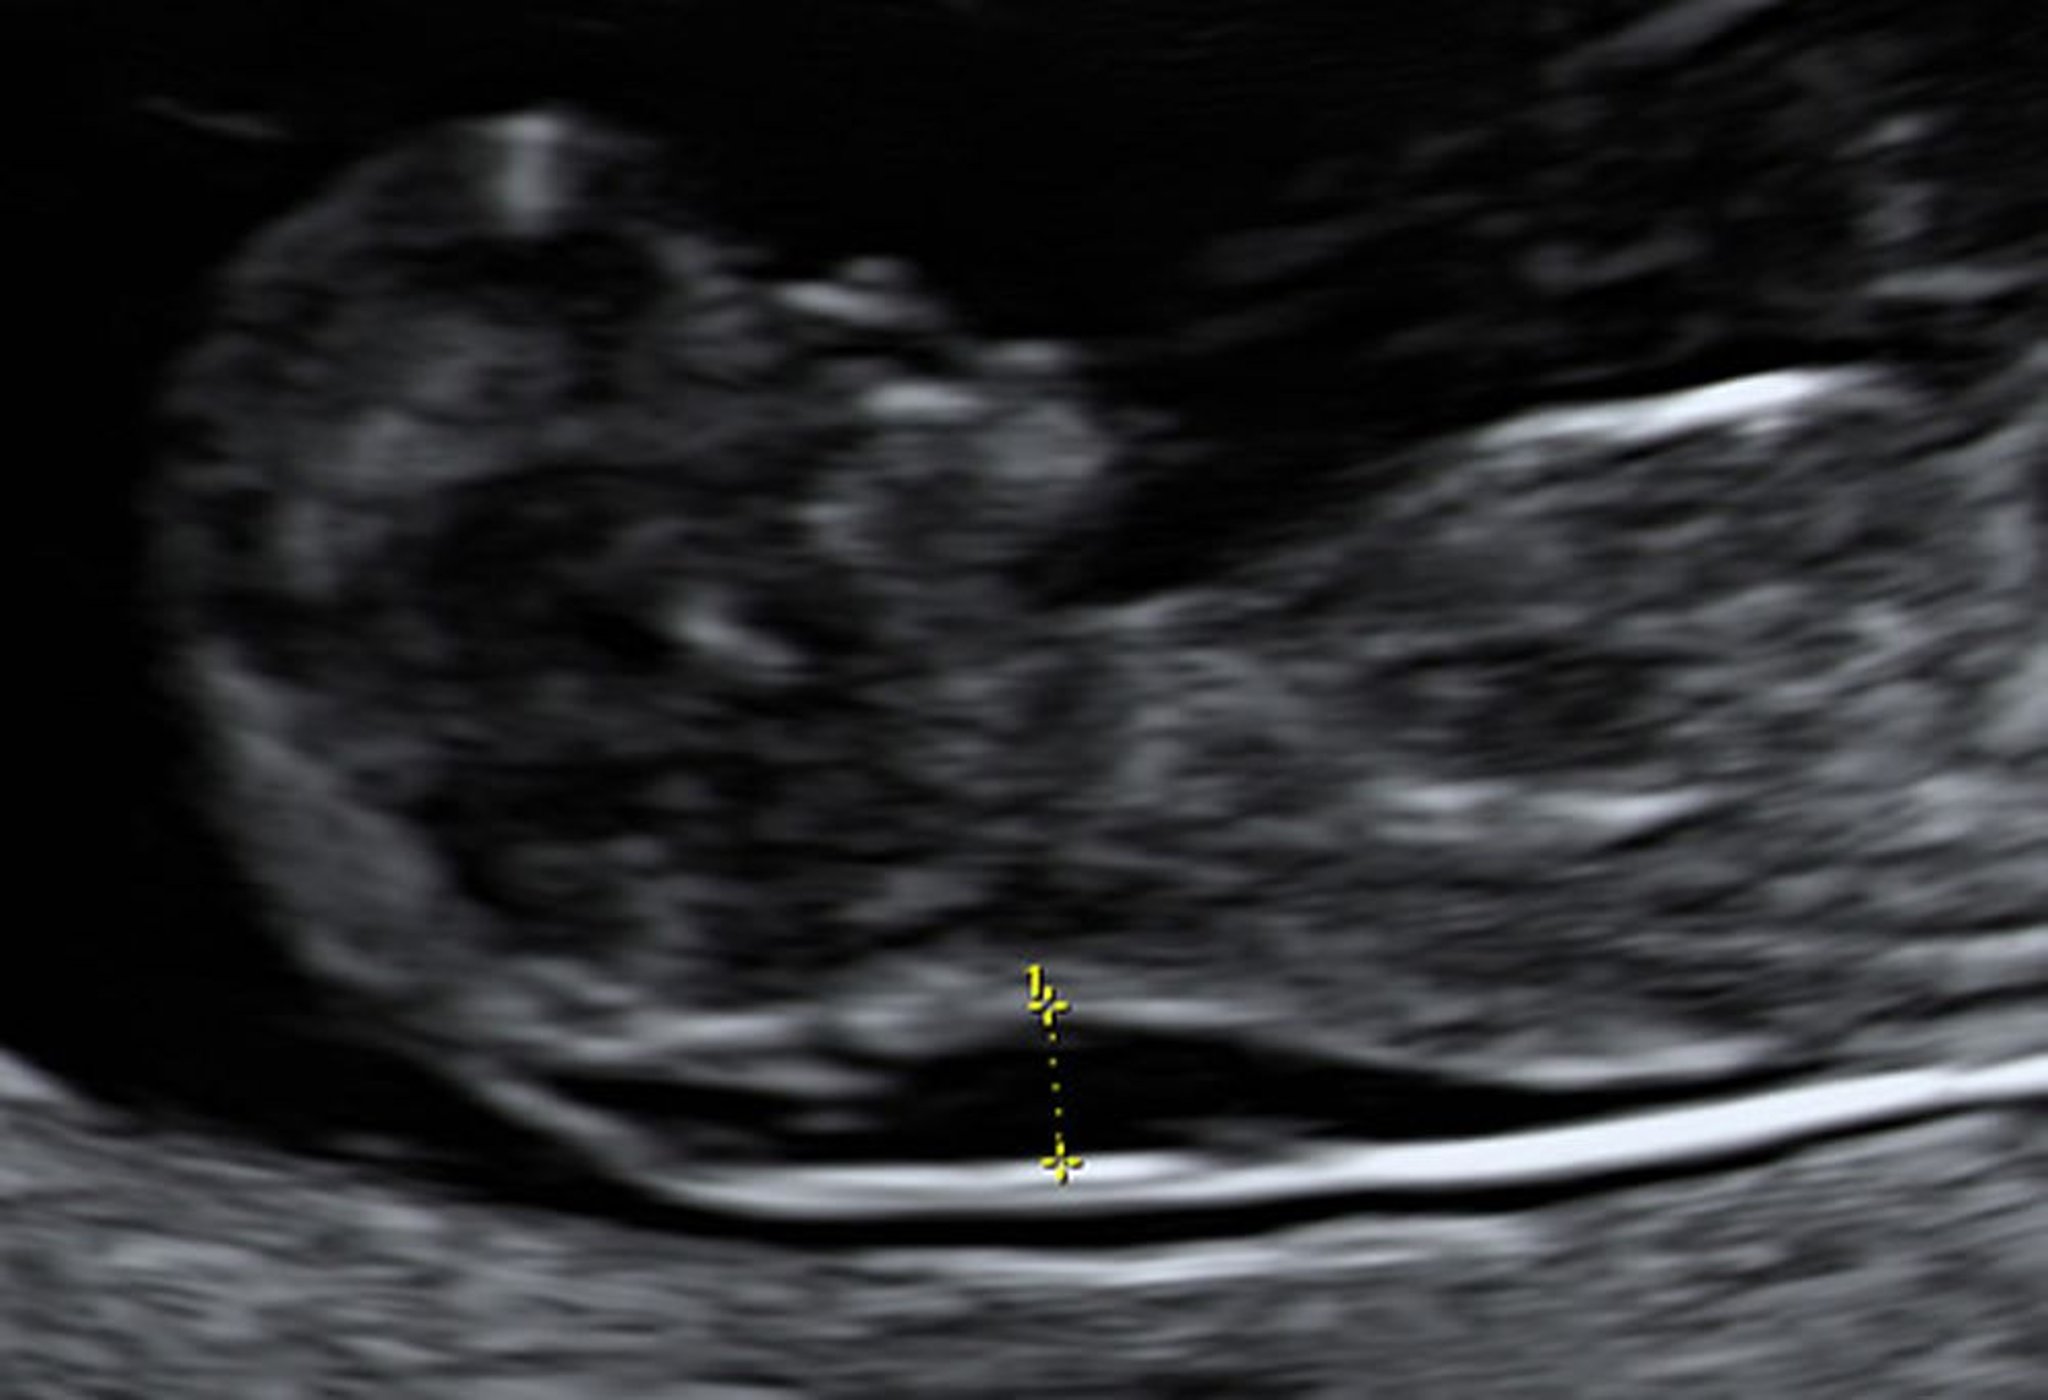

Siêu âm cho thấy khoảng mờ của da gáy to ra ở thai nhi 10 tuần

Lấy mẫu nhung mao màng đệm cho thấy thai nhi này mắc hội chứng Down.

Hình ảnh do bác sĩ Jeffrey S. Dungan cung cấp.